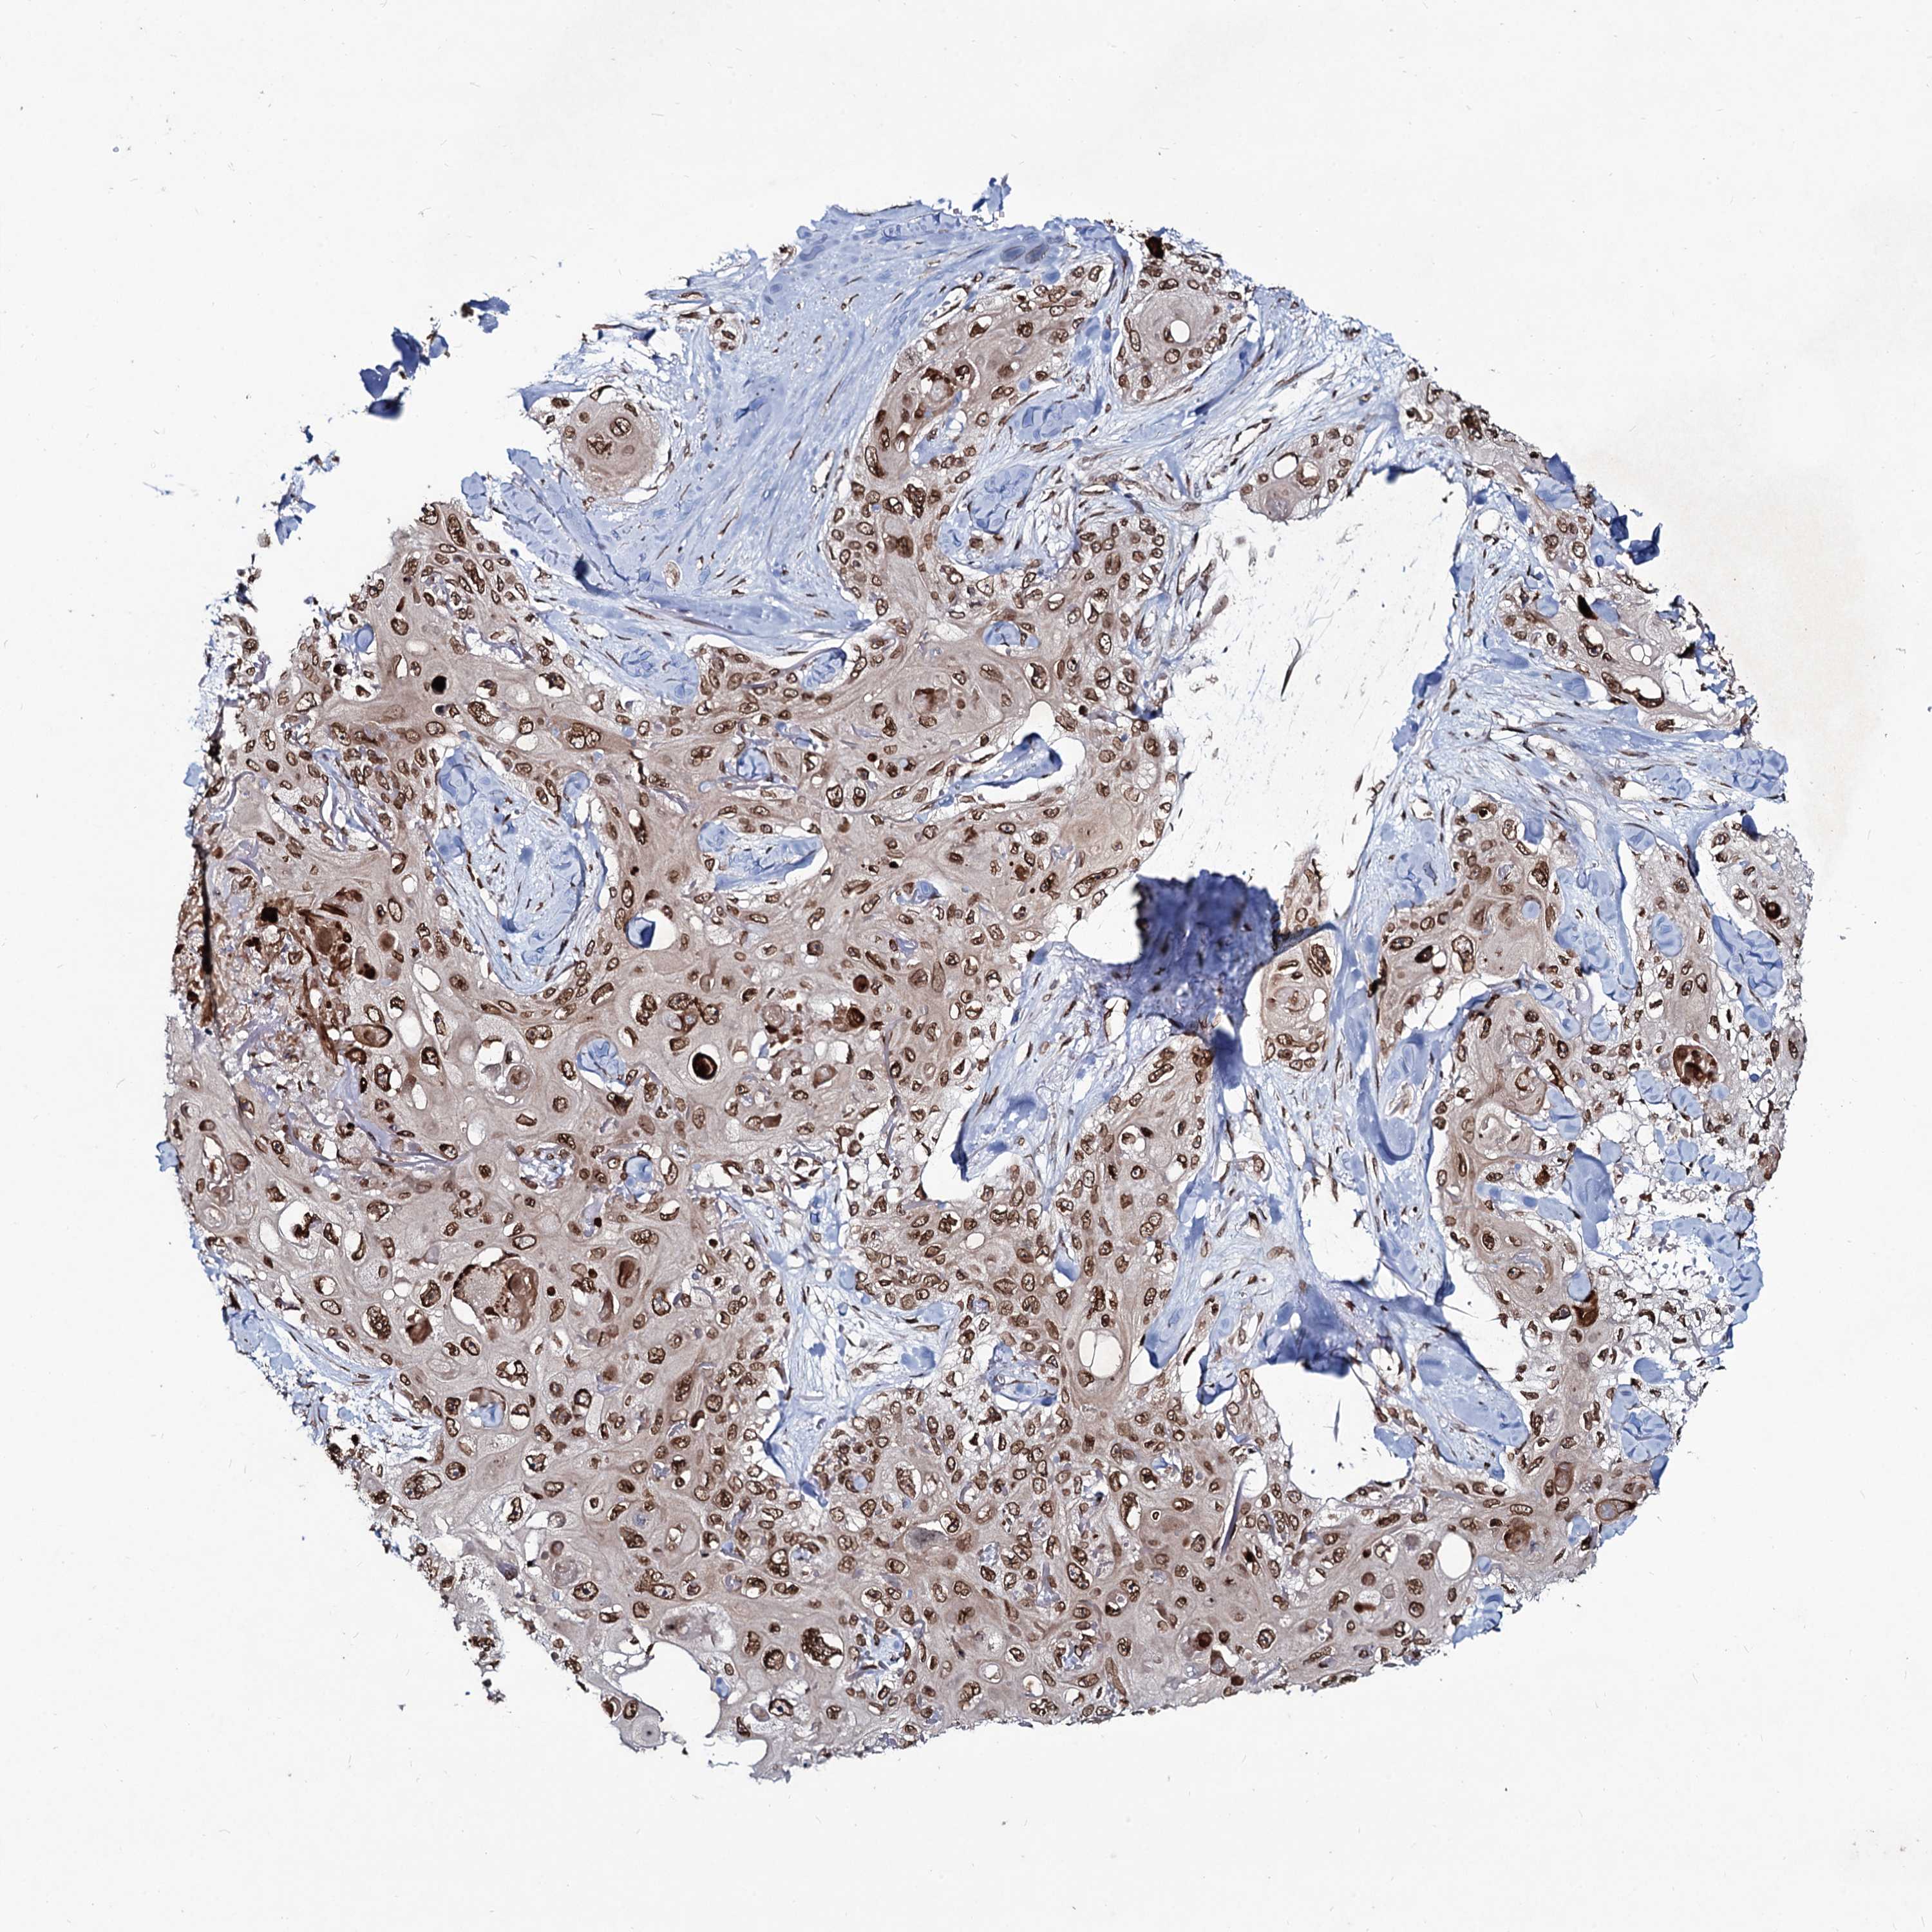

SKIN CANCER - Protein expressioni

A mouse-over function shows sample information and annotation data. Click on an image to view it in a full screen mode. Samples can be filtered based on level of antibody staining by selecting one or several of the following categories: high, medium, low and not detected. The assay and annotation is described here.

Each image is clickable and will lead to virtual microscopy that enables deeper exploration of all samples and also displays staining intensity scores, fraction scores and subcellular localization as well as patient and tissue information for each sample.

Antibody HPA040048

Squamous cell carcinoma, NOS